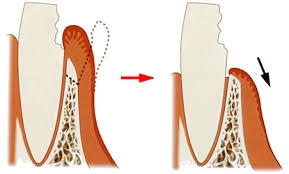

クラウンレングスニング(歯肉形成術)

クラウンレングスとは、歯冠延長術とも呼ばれる歯茎の処置の治療法です。